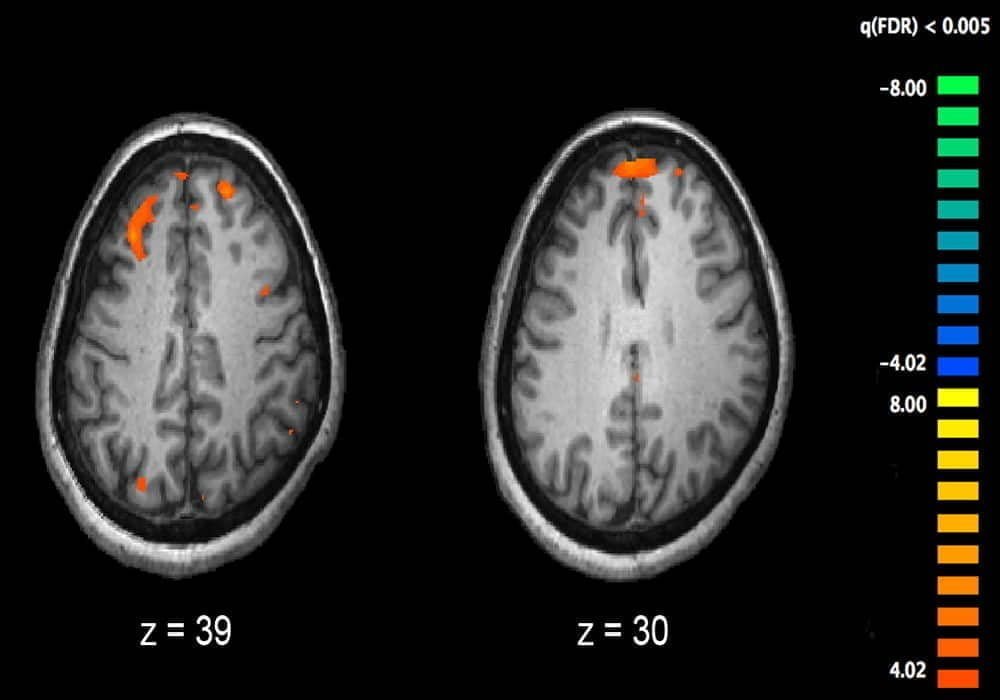

Skizofrenia adalah penyakit mental yang memengaruhi bagaimana seseorang berpikir atau merasa. Penderitanya seringkali tidak bisa membedakan antara kenyataan dan sebaliknya.

Keadaan ini pada umumnya dimanifestasikan dalam bentuk halusinasi pendengaran, paranoid atau waham yang ganjil, atau cara berbicara dan berpikir yang kacau, dan disertai dengan disfungsi sosial dan pekerjaan yang signifikan.

Hal terpenting adalah menciptakan hubungan dengan pasien, aliansi terapeutik, sehingga ia mengikuti pengobatan dan belajar memahami penyakitnya dan gejalanya. Kemudian, bisa ada pendekatan farmakologis, dengan neuroleptik dan antipsikotik yang memungkinkan untuk menyeimbangkan kembali konsentrasi neurotransmiter – termasuk dopamin – dan dengan demikian mengurangi gejala penyakit.